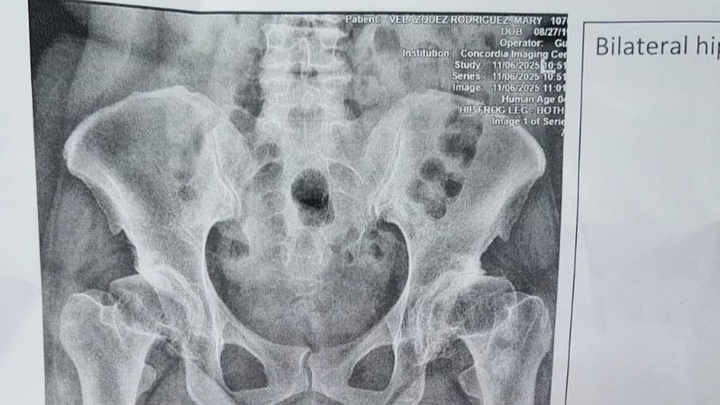

Bendecido, necesito de su ayuda para cubrir gastos médicos ( deducible que el plan médico no cubre); para remplazo de ambas caderas. Es importante para mí ya que no puedo caminar normalmente , soy una persona joven y deseo volver a tener una vida activa y normal.